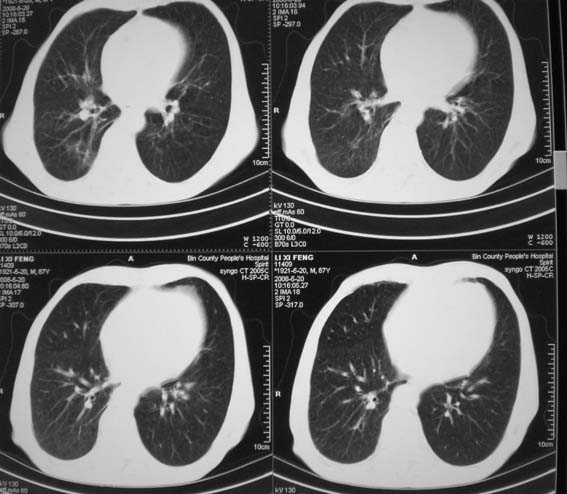

男,87岁,咳嗽、发烧、有黄痰,胸片示肺结核。

右侧上叶结核,干酪性肺炎,慢支

右肺上叶尖后段片状不规则致密影,密度欠均匀,相邻胸膜肥厚,纵隔内见多发肿大、钙化淋巴结,考虑为结核,部分坏死